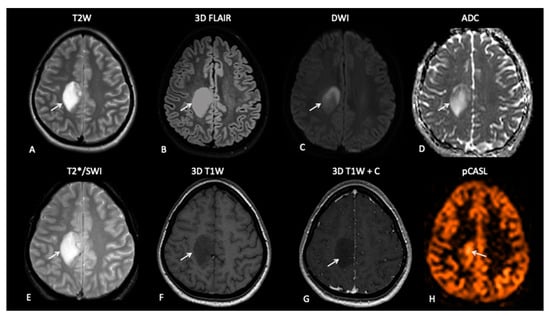

Standard basic minimal anatomical MRI for paediatric brain tumour imaging includes axial fluid-attenuated inversion recovery (FLAIR) and T2-weighted sequences visualizing non-enhancing tumour components, oedema and therapy induced-gliosis, diffusion weighted imaging (DWI) to aid the assessment of therapy response and high-resolution 3D isotropic pre- and post-contrast enhanced T1-weighted sequences to depict contrast leakage from the tumour vessels (Figure 1) [43]. Whilst international standard brain MRI protocols exist for adults [44], no such recommendations exist for paediatric neuro-oncology [45]. At our institution, we follow the adult MRI recommendations but also include a blood sensitive sequence such as T2* or susceptibility weighted imaging (SWI) to depict intra-tumoural haemorrhage and the development of radiation-induced cavernomas, and to depict biopsy tracts [46] and arterial spin labelling (ASL) perfusion to aid in the assessment of gliomas post-treatment [47]. Table 1 demonstrates the parameters for our paediatric/TYA neuro-oncology MRI protocol.

Figure 1.

Nineteen-year-old female presenting with epilepsy. MRI demonstrates a well-defined T2W (A), FLAIR (B), DWI (C) and a hyperintense lesion with a medial border of restricted diffusion on an apparent diffusion coefficient (ADC) map (D). The lesion demonstrates no areas of susceptibility (E) and no pathological enhancement on pre- and post-contrast T1W images (F,G). The appearances are consistent with low-grade glioma, but pCASL perfusion-weighted imaging (PWI) (H) demonstrates medial increased perfusion.